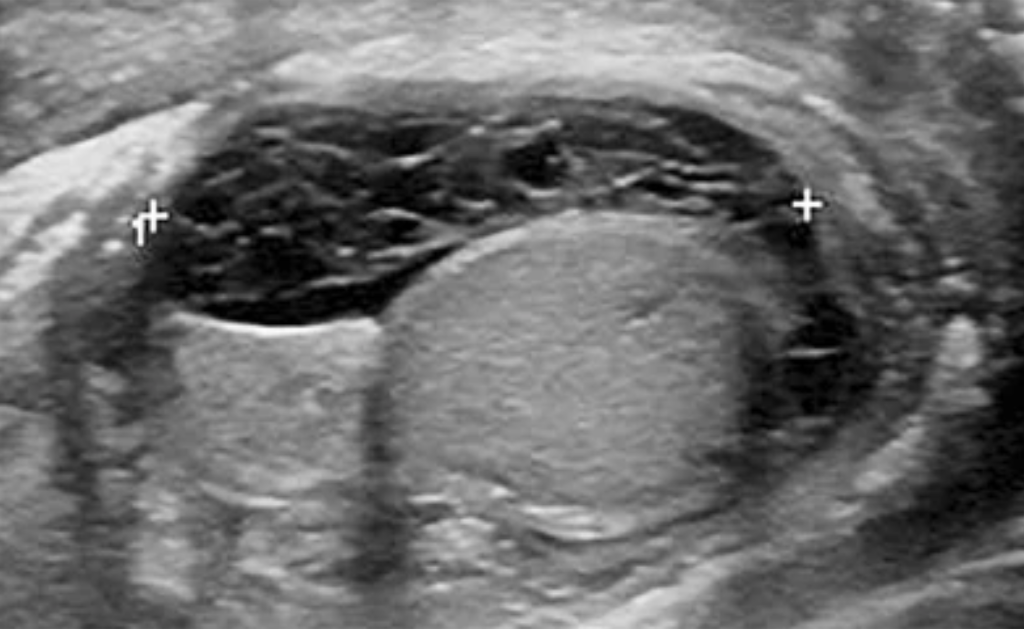

Testicular Rupture. Source: Blok et al., 2019

- Findings: Ultrasound shows discontinuity of the tunica albuginea, heterogeneous echotexture, and extrusion of testicular contents, often with associated hematocele or hemorrhage.

- Sensitivity: 100%; Specificity: 93.5% (Buckley & McAninch, 2006)

- Management: Urgent surgical exploration and repair.